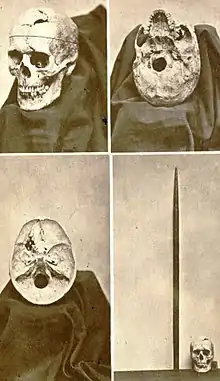

In April 1849, Gage returned to Cavendish and visited Harlow, who noted at that time loss of vision, and ptosis, of the left eye,[note 8] a large scar on the forehead (from Harlow's draining of the abscess)[H1]: 392 and

upon the top of the head ... a quadrangular fragment of bone ... raised and quite prominent. Behind this is a deep depression, two inches by one and one-half inches [5 by 4 cm] wide, beneath which the pulsations of the brain can be perceived. Partial paralysis of the left side of the face. His physical health is good, and I am inclined to say he has recovered. Has no pain in head, but says it has a queer feeling which he is not able to describe.[H]: 12-13

Gage's rearmost left upper molar, adjacent to the point of entry through the cheek, was also lost.[note 9] Though a year later some weakness remained,[M]: 93 [24] Harlow wrote that "physically, the recovery was quite complete during the four years immediately succeeding the injury".[H]: 19

In addition, Ratiu et al. noted that the hole in the base of the cranium (created as the tamping iron passed through the sphenoidal sinus into the brain) has a diameter about half that of the iron itself; combining this with the hairline fracture beginning behind the exit region and running down the front of the skull, they concluded that the skull "hinged" open as the iron entered from below, then was pulled closed by the resilience of soft tissues once the iron had exited through the top of the head.

Van Horn et al. concluded that damage to Gage's white matter (of which they made detailed estimates) was as or more significant to Gage's mental changes than cerebral cortex (gray matter) damage.[V]: abstr Thiebaut de Schotten et al. estimated white-matter damage in Gage and two other case studies ("Tan" and "H.M."), concluding that these patients "suggest that social behavior, language, and memory depend on the coordinated activity of different [brain] regions rather than single areas in the frontal or temporal lobes."[T1]: 12

Ratiu et al. and Van Horn et al. both concluded that the tamping iron passed left of the superior sagittal sinus and left it intact, both because Harlow does not mention loss of cerebrospinal fluid through the nose, and because otherwise Gage would almost certainly have suffered fatal blood loss or air embolism.